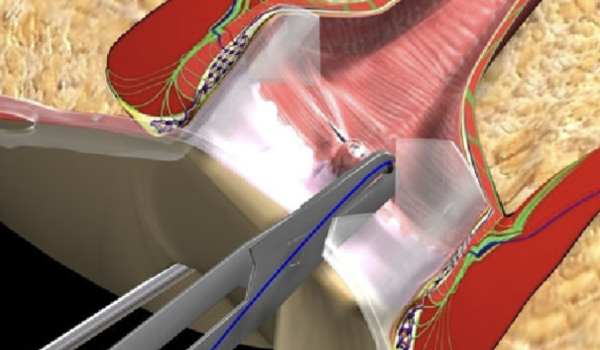

Recomendaciones de mejores prácticas clínicas de un grupo internacional de cirujanos con amplia experiencia en el procedimiento FiLaC para el tratamiento de fístulas anales con tecnología láser.